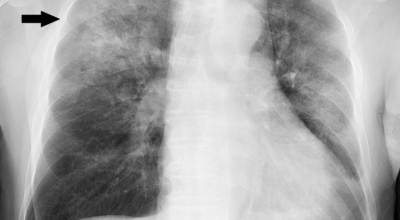

폐렴 증상이 있는 경우 X선 촬영 및 배양 검사로 진단할 수 있답니다. 필요에 따라 소변, 혈액, 혈청 검사, CT 등을 추가로 실시합니다. 폐렴 진단을 받은 환자는 일반적으로 입원을 권장하지 않지만 젊거나 기초질환이나 호흡곤란이 심한 경우, 고령, 임신 등의 경우 병원에 내원하여 상황에 맞는 신속한 치료와 상태 개선, 위험관리를 받는 게 좋아요.